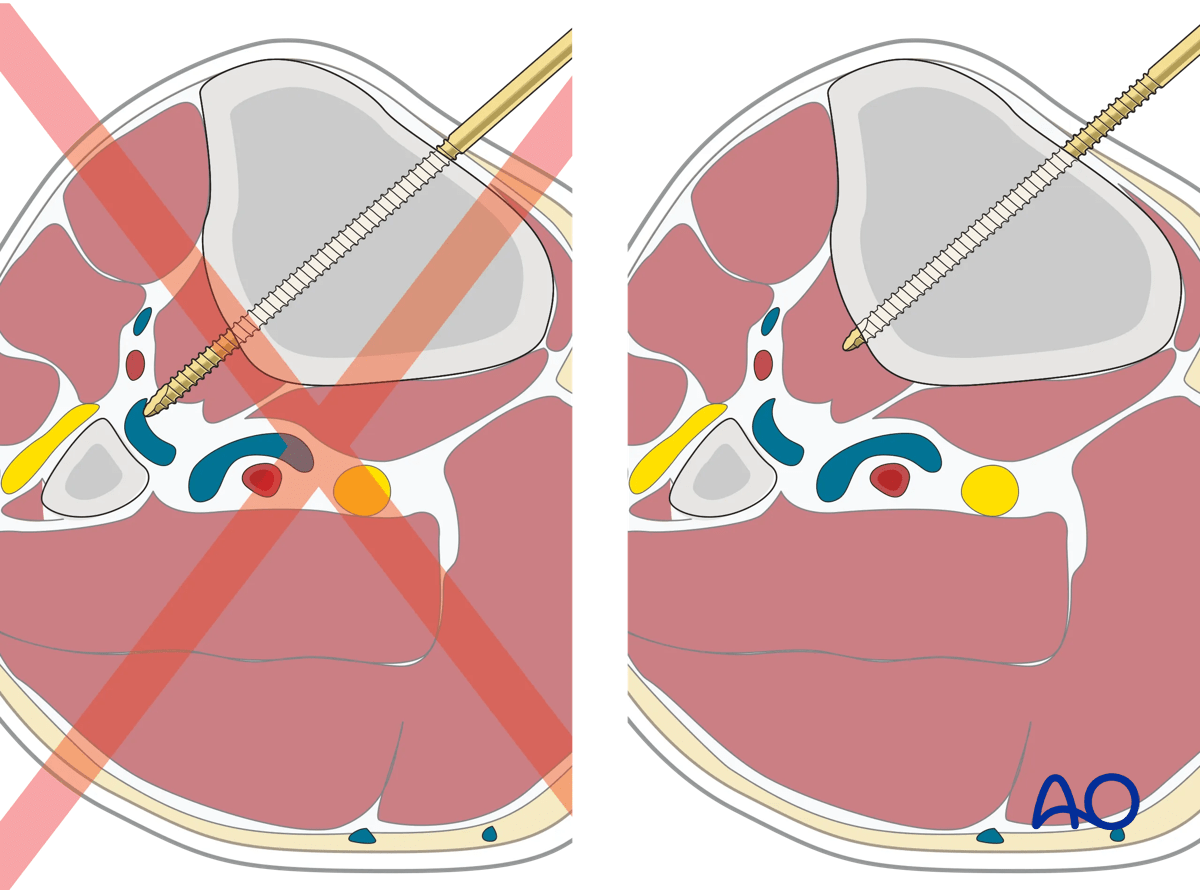

7. Options for Schanz screw placement

Schanz pins in the tibia are generally placed from the medial side (anteromedially, direct medial, or posteromedial). Pin divergence within the safe zone helps to optimize biomechanical stability of the frame.

Note: Care must be taken not to over insert Schanz screws. The exposed tips represent a neurovascular risk. In the case of blunt tipped Schanz screws, it is recommended that the screws are advanced an average of two threads past the far cortex.

Proximal tibia fracture – ring fixation: care must be taken not to over insert Schanz screws